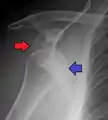

A diagnosis of shoulder dislocation is often suspected based on the person's history and physical examination. Radiographs are made to confirm the diagnosis. Most dislocations are apparent on radiographs showing incongruence of the glenohumeral joint. Posterior dislocations may be hard to detect on standard AP radiographs, but are more readily detected on other views. After reduction, radiographs are usually repeated to confirm successful reduction and to detect bone damage. After repeated shoulder dislocations, an MRI scan may be used to assess soft tissue damage. In regards to recurrent dislocations, the apprehension test (anterior instability) and sulcus sign (inferior instability) are useful methods for determining predisposition to future dislocation.

Posterior dislocations are uncommon, and are typically due to the muscle contraction from electric shock or seizure.[6] They may be caused by strength imbalance of the rotator cuff muscles. People with dislocated shoulders typically present holding their arm internally rotated and adducted, and exhibiting flattening of the anterior shoulder with a prominent coracoid process.

Posterior dislocations may go unrecognized, especially in an elderly person[12] and in people who are in the state of unconscious trauma.[13] An average interval of 1 year was noted between injury and diagnosis in a series of 40 people.[14]